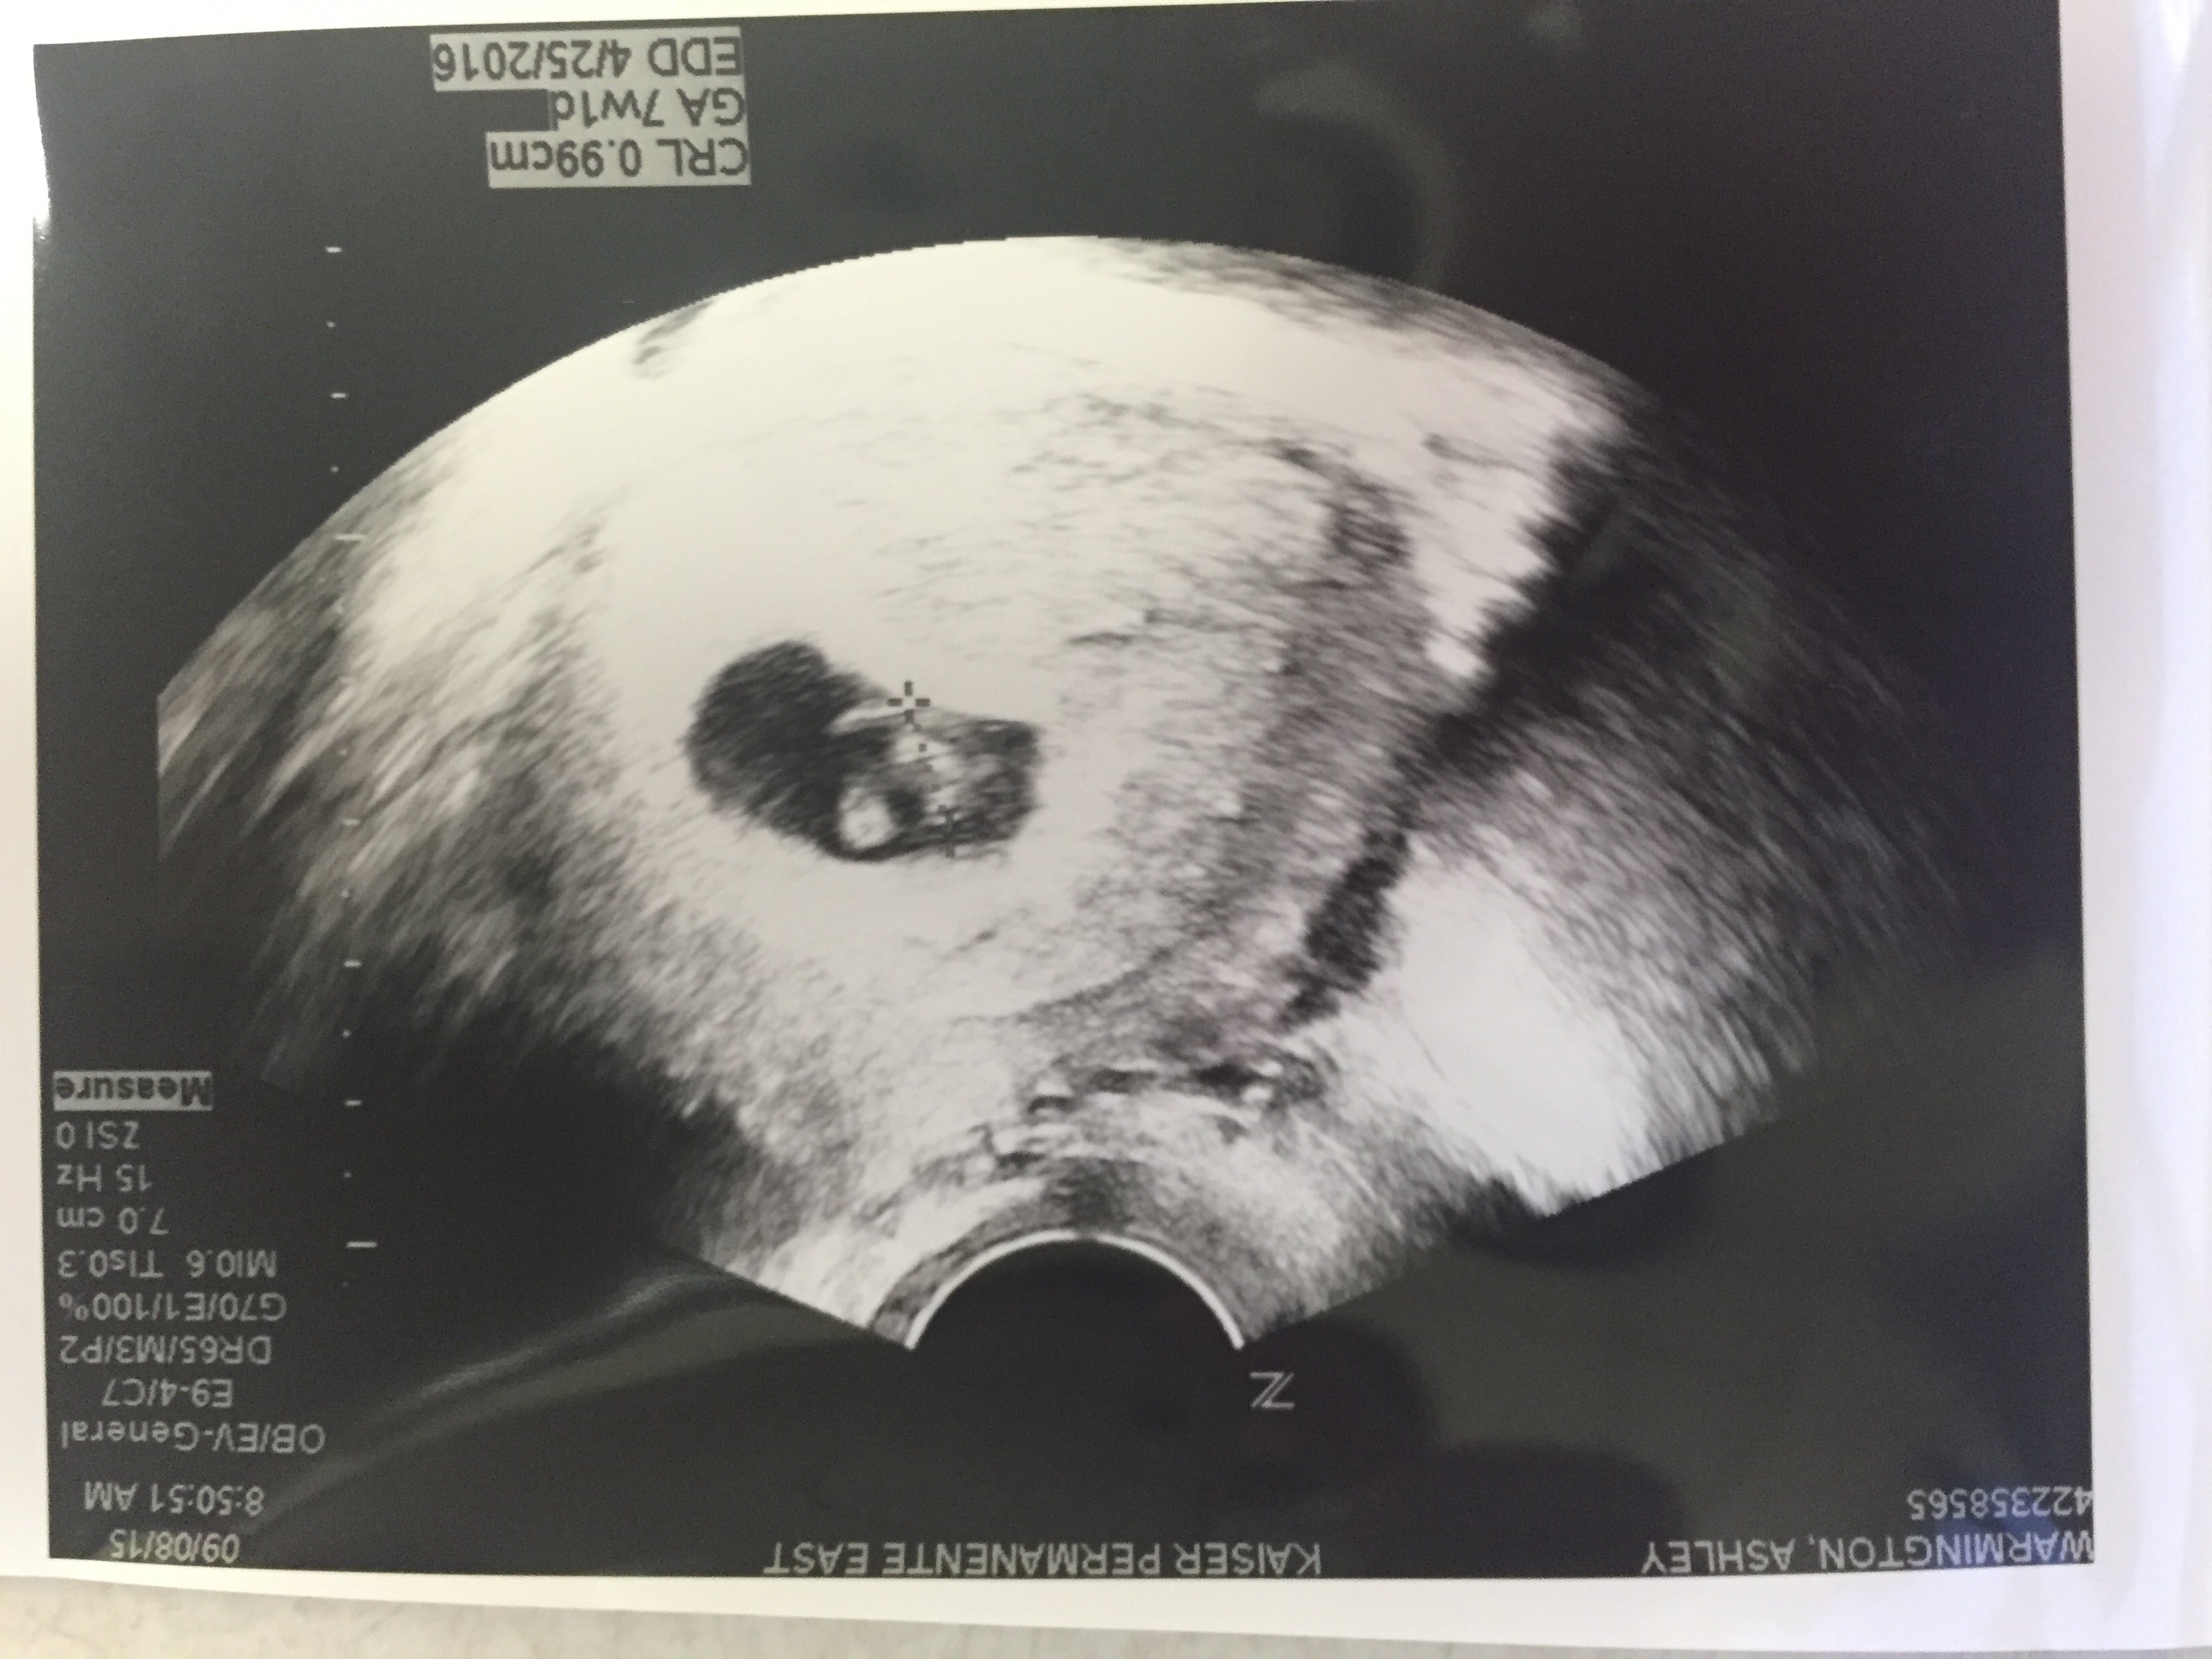

We have a heartbeat !!!!!!!

First appt this morning at 7weeks 1 day and we have a good strong heartbeat!!!!!!!!! After a MMC in March I can't begin to explain how relieved we are. I know we still have a long road ahead and many things can go wrong but today more than any day I am so grateful to be pregnant! Good luck to all you ladies. April can't come soon enough  :):):)